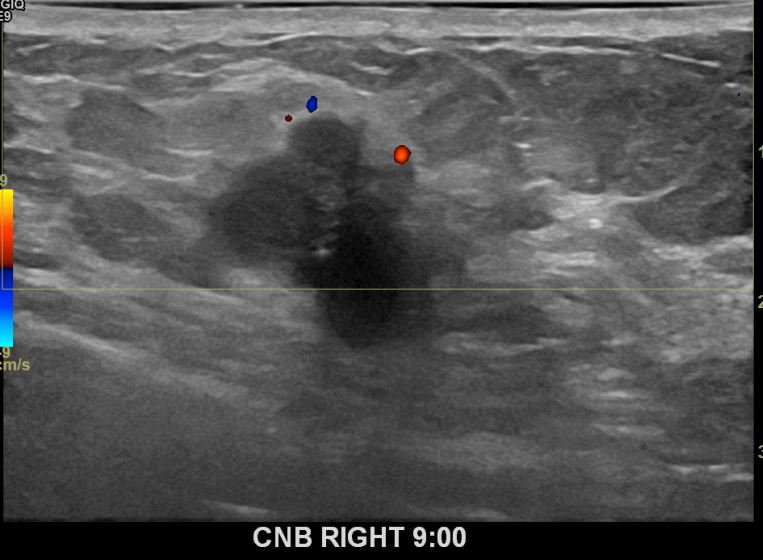

아산유외과개원후 701번째 유방암진단

상기환자 우측유방에 딱딱한 멍울이만져져 내원하신 60대여성분으로 우측유방의 혹 조직검사시행후 유방암 진단되었습니다